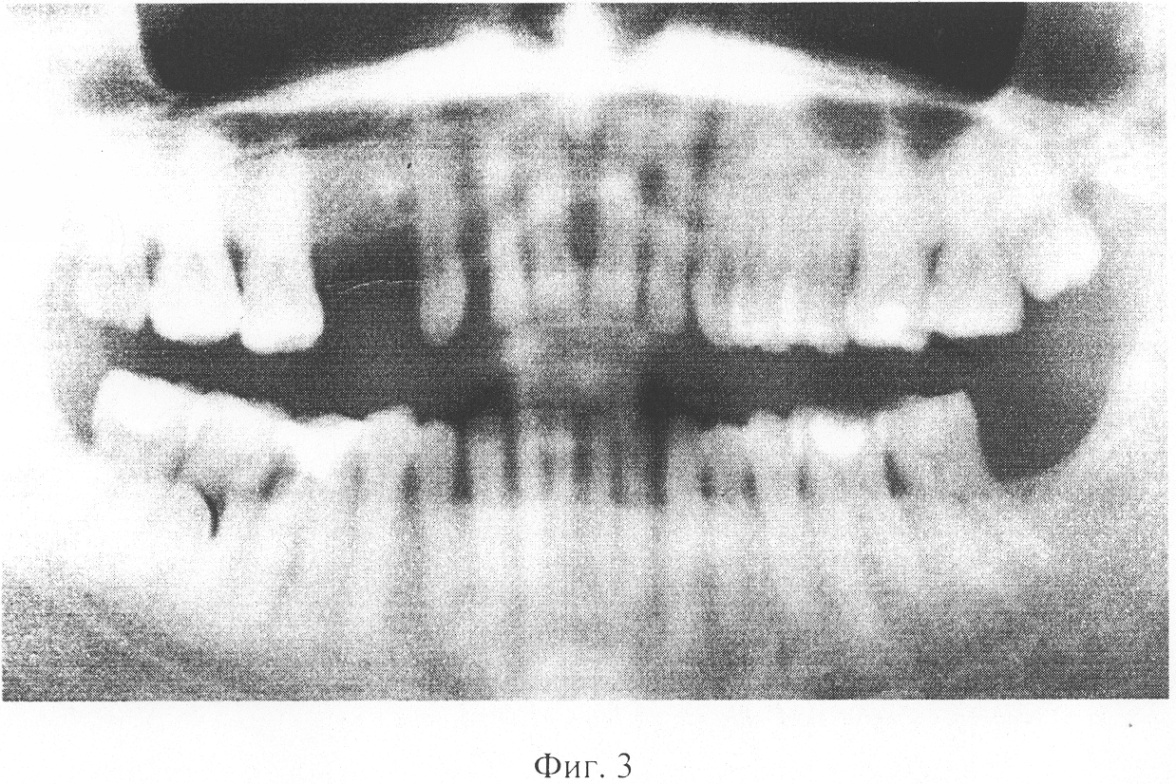

на фиг.3 – панорамный дентальный рентгеновский снимок, полученный на ортопантомографе «ORTORALIX»

На фиг.3 и фиг.4 представлены два снимка – полученный на аппарате с протяженным фокусным пятном (0.7 мм в диаметре, фиг.3) и полученный на микрофокусном аппарате (менее 0.1 мм в диаметре, фиг.4).

Снимки отсканированы таким образом, что их разрешение составляет 1500×1000 пикселей притом, что исходный размер составлял 300 на 200 мм. Ввиду примерной одинаковости видимых размеров деталей на снимках возможно их корректное сравнение.

Проведенный по формуле (3) анализ дал следующие результаты: Q для снимка с протяженным фокусным пятном составляет 15, а Q для снимка на микрофокусном источнике составляет 530.

В соответствии с заявляемым способом было проведено сравнение 8 снимков, полученных на аппарате с протяженным фокусным пятном, и 7 – на микрофокусном источнике. Среднее значение Q для традиционных снимков составило 12,5 при разбросе значений от 9 до 26, среднее значение для микрофокусных снимков составило 462,4 при разбросе значений от 380 до 625.